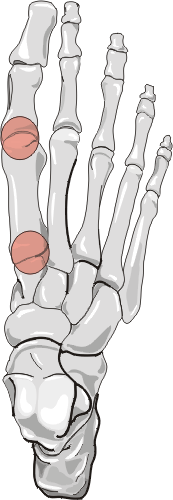

The first metatarsal phalangeal and first tarsometatarsal joints are most commonly affected with osteoarthritis of the foot. The dorsal talonavicular joint is also commonly involved. The remaining metatarsal phalangeal and interphalangeal joints are affected to a lesser degree. Plantar or posterior calcaneal spurring may also occur. The disease distribution may be uni- or bilateral.

Radiographic manifestations may include marginal osteophyte and subchondral bony cyst formation, eburnation, and interosseous joint space narrowing. First metatarsal phalangeal joint osteoarthritis is frequently associated with hallux valgus deformities. Calcaneal spurs, when manifested, are sharp and well defined.